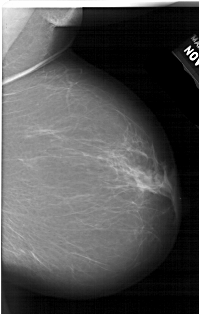

A_1519_1.LEFT_CC

LEFT_CC LINES 6871 PIXELS_PER_LINE 4021 BITS_PER_PIXEL 12 RESOLUTION 43.5 OVERLAY